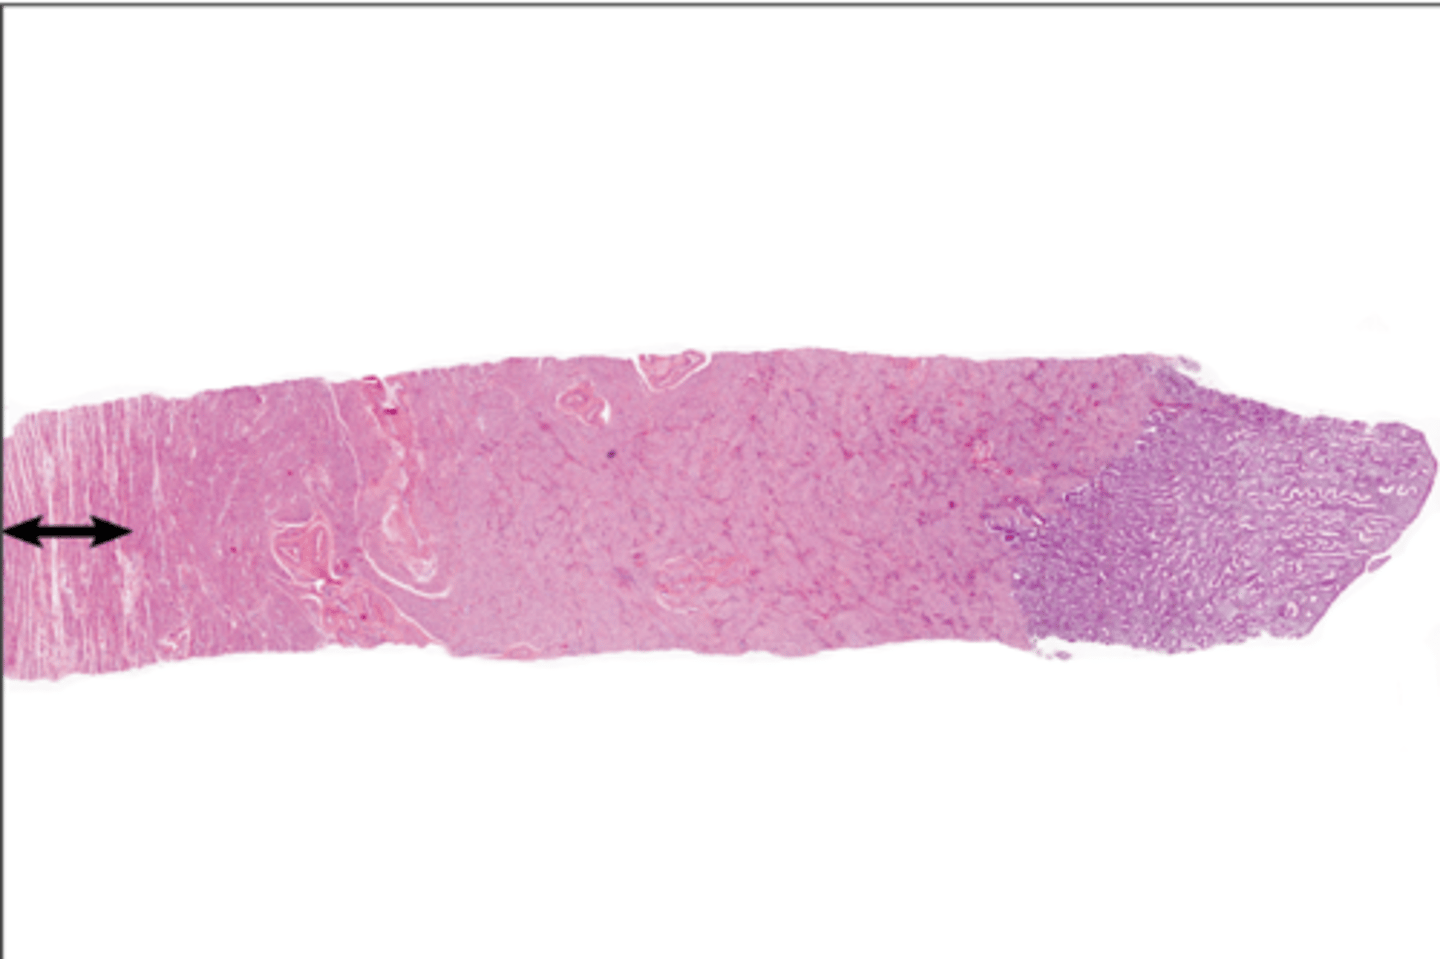

proliferate functional layer

secretory functional layer

menstrual functional layer

proliferate basal layer

secretory basal layer

menstrual basal layer

Endometrium

Endometrium

Myometrium

Myometrium